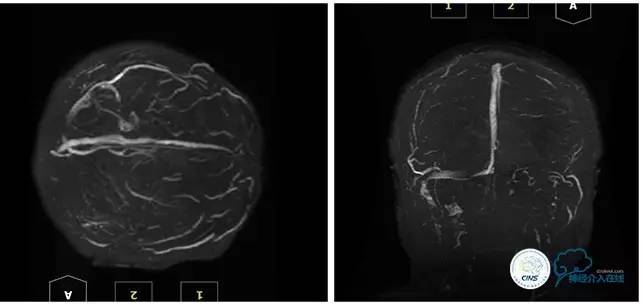

MRV

2016-05-20 MRV